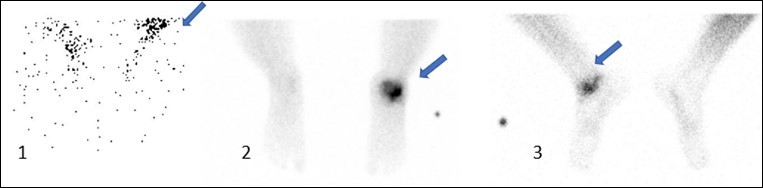

Three phase Bone scan : Increased flow (1) indicates preserved blood supply to graft region along with increased blood pooling in the (2) image with spot (3) at delayed 3hr reveals increased tracer uptake ascertaining the integrity and viability of the bone allograft

SPECT/CT depicting increased tracer uptake after one month at the site of allogenic bone grafting (same above patient) done for avascular necrosis right talus.